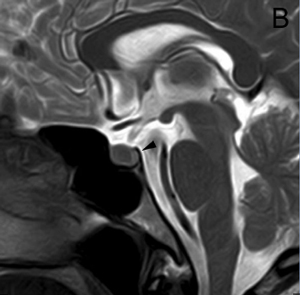

Figura 15 A, B y C. Cortes sagital T1w, coronal T1w Gad. y coronal T2w. Absceso pituitario que simula un macroadenoma quístico no funcionante.El compromiso del seno cavernoso (definido como la invasión perivascular de la arteria carotida interna), se observa en 19% de los macroadenomas y es habitualmente unilateral (Figuras 16A, 16B y 16C) pero puede ser bilateral en macroadenomas invasores (Figuras 17A y 17B). Para evaluar la invasión del seno cavernoso se utilizan las imágenes coronales T1w con gadolinio, efectuando el análisis de la forma y compartimientos del seno cavernoso y su relación con el adenoma; cuando el porcentaje de tumor que rodea la arteria carótida interna intracavernosa es mayor o igual a 66% del círculo medido alrededor de la carótida, hay invasión del seno, si es menor de 25%, el seno no está invadido48.

Figura 16A, B y C. Cortes coronales T1w sin y con Gadolinio y T2w. Macroadenoma con expansión asimétrica de la silla turca e invasión del seno cavernoso izquierdo.

Figura 17A y B. Cortes coronal y axial transversal, T1w Gad. Macroadenoma con crecimiento hacia lateral (entre puntas de flecha), mayor a derecha con invasión de ambos senos cavernosos; el quiasma está libre.Los adenomas invasores (Figuras 18 y 19) constituyen un grupo aparte y de acuerdo con series recientes publicadas representan entre 10% a 35% de los adenomas pituitarios operados49. En estos casos el potencial de invasión es estimado con mayor precisión con estudios histoquímicos y ultraestructurales de las muestras obtenidas durante la cirugía. Estos estudios patológicos, en conjunto con la cuantía de tumor residual demostrada con las neuroimágenes postoperatorias, definirán la conducta terapéutica a seguir.